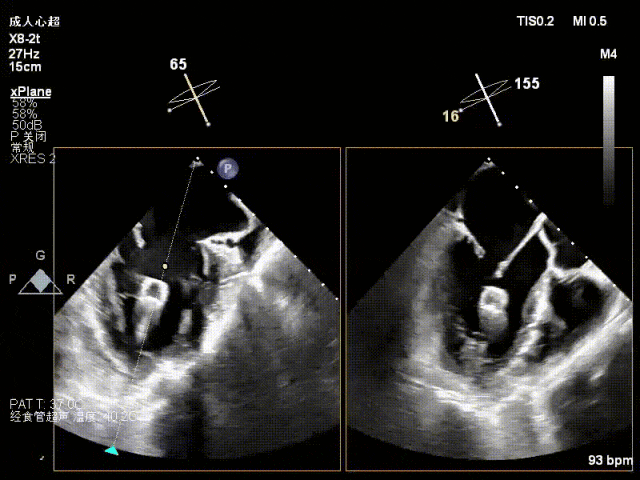

术中超声(关键步骤)

术前术后对比图

术前

术后